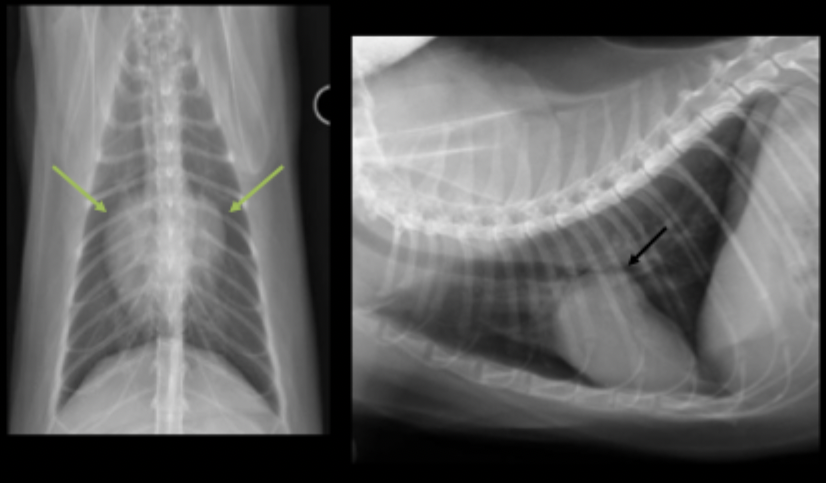

What can be seen in these radiographs?

subaortic stenosis/stenotic aortic valve

How does subaortic stenosis/stenotic aortic valve appear on radiograph?

enlargement of the aortic arch due to turbulent blood flow (11-1 o’clock(

elongation of the left ventricle due to hypertrophy